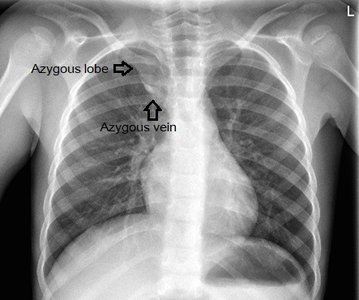

Lobe of Azygos Vein and Accessory Lung

Lobe of Azygos Vein: An anatomical variant appearing in the right lung, visible on chest X-ray.